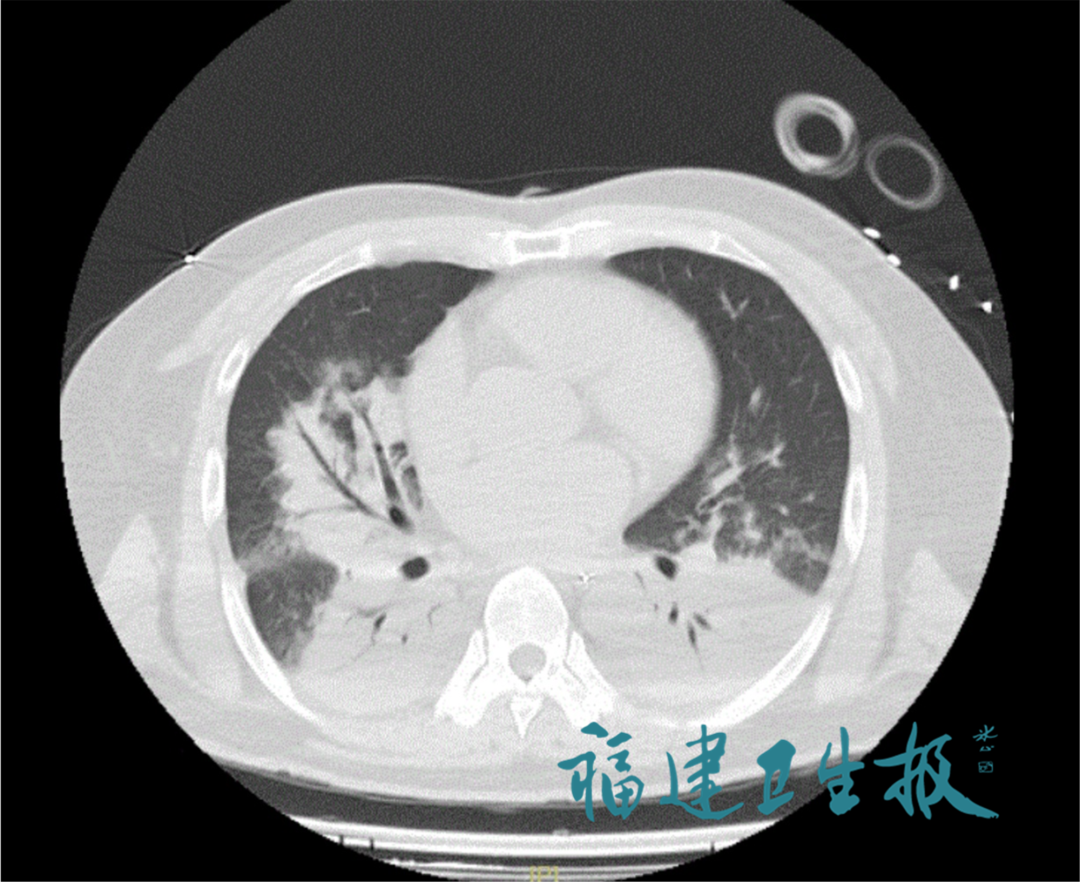

此前,当地医院检查发现,他的肺部已出现大面积“白肺”,血氧饱和度骤降至70%,生命垂危。经气管插管和呼吸机支持后,陈先生缺氧的症状有所缓解,在当地医院的建议下,立即转至附一医院。

考虑到陈先生病情危重、进展快,附一医院紧急将其转到急诊EICU治疗。从影像和症状判断,陈先生都比较符合“军团菌肺炎”。